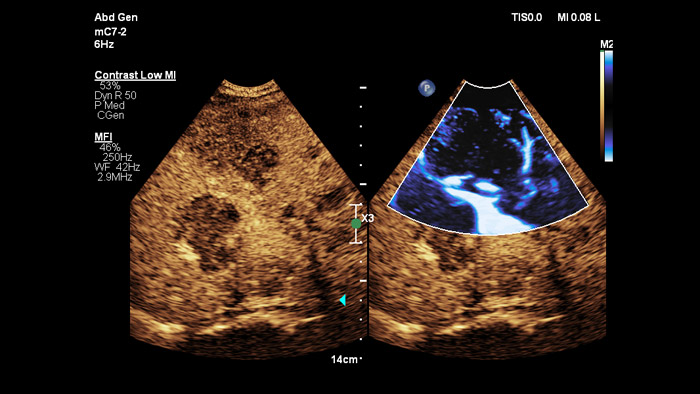

ElastQ proporciona una evaluación en tiempo real de la rigidez tisular de onda de corte 2D (2D-SWE) no invasiva, reproducible y fácil de realizar. ElastQ también ofrece la posibilidad de realizar mediciones retrospectivas en imágenes almacenadas e incluye un mapa de fiabilidad para una visualización adecuada de la propagación de la onda de corte.

ElastQ imaging